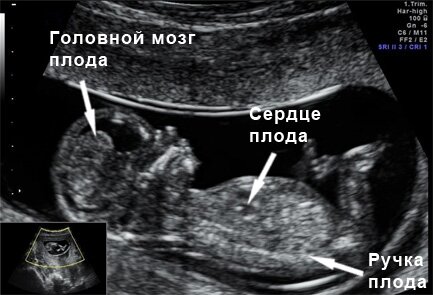

Самое дорогое для любой мамы- это знать,что сердце ее ребенка бьется.Сердечно-сосудистая система в организме человека начинает развиваться сомой первой.Уже на первой неделе развития вашего малыша появляются первые зачатки сердечно-сосудистой системы.На 22 день после зачатия отмечается пульсация будущего сердца,а на 26 день начинает циркулировать кровь у эмбриона,который всего 3 мм.Первый раз можно услышать биение сердца вашего малыша уже на пятой недели беременности на УЗИ трансвагинальным методом при наличии хорошей аппаратуры, а на 8 неделе можно услышать уже через брюшную стенку(трансабдоминальное обследование). В 12 недель на плановом обследовании УЗИ сердце должно быть четырех-камерным, как у взрослого человека.

По сердцебиению плода можно судить о количестве поступаемого кислорода ребенку.С 21 недели беременности врач может выслушать сердцебиение ребенка при помощи акушерского стетоскопа.С каждой неделей развития ребенка сердцебиение меняется.